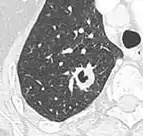

Lobulated nodule.[9]